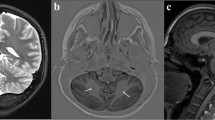

Human cerebellar malformations are diverse and commonly recognized birth defects, frequently associated with significant developmental disabilities [1]. Dandy–Walker malformation (DWM) is one of the most well-known cerebellar malformations, first recognized and defined by autopsy studies from the late 1860s to 1950s [7, 12, 32]. DWM is now diagnosed by brain imaging studies (Fig. 1a, b, d–f) and strictly defined by cerebellar hypoplasia predominantly affecting the posterior vermis, upward rotation of the cerebellum away from the brain stem causing elevation of the tentorium (Fig. 1b, white arrowhead), and a dilated fourth ventricle (Fig. 1b, c, asterisk) within an enlarged posterior fossa (Fig. 1b, red arrowhead) [5, 6, 8]. DWM can occur in isolation or as part of syndrome including other congenital defects [1, 2].

Cerebellar morphobiometry in Dandy–Walker malformation (DWM). Postnatal MRI through midsagittal plane in normal (a) and DWM (b), with the ‘tail sign’ indicated (white arrowhead). DWM is characterized by cerebellar vermis hypoplasia, a dilated 4th ventricle (white asterisk) and an enlarged posterior fossa (red arrowhead). Midsagittal section of a 24pcw DWM hindbrain shows characteristic ‘tail sign’ (white arrowhead) and hypoplasia of the vermis (c). Fetal MRI in normal (d) and DWM (e, f), where tegmento-vermian angle (red), cranio-caudal diameter (green) and antero-posterior diameter (yellow) are measured and shown as dashed lines. Measurements for APD, CCD, and TVA in five normal cases (table, grey) and six DWM cases (table, orange) are compared. Data is represented in percentiles and mean ± standard error of mean

While there is a consensus regarding the distinctive postnatal brain imaging features of true DWM, the developmental origins of these features remain unclear and prenatal diagnosis has historically been difficult with poor correlation between prenatal imaging and postnatal outcome [9, 10, 27, 28, 31]. Recently, imaging studies have suggested that a “tail sign”, an aberrant posterior vermis lobule extending into an enlarged fourth ventricle, represents a diagnostic feature of prenatal DWM and distinguishes DWM from other cerebellar malformations (Fig. 1b, c, white arrowhead) [8]. Since there is limited literature on the prenatal or postnatal pathology of human DWM [13, 22, 30], the origin of this tail and its relationship to postnatal DWM pathology remain unclear.

Fetal and postnatal imaging

Upward rotation of cerebellar vermis in Dandy Walker malformation

We studied the histopathology of a total of 31 cerebellar malformation cases between 15 and 34 post-conception weeks (pcw) from multiple centers (Suppl. Fig. S1, 2; Suppl. Table S1; online resource). Centers independently diagnosed 26 cases as DWM and 5 as CVH following an initial ultrasound followed by fetal MRI, with diagnosis confirmed by pathology. For 6 DWM cases we obtained imaging files and performed morphobiometric analyses of the cerebellum, measuring: a) vermian antero-posterior diameter (APD), b) vermian cranio-caudal diameter (CCD) and c) the tegmento-vermian angle (TVA), as defined previously [11, 35] (Fig. 1d–f; table). The vermian APD and CCD for all of the cases studied was below the 5th percentile, while the TVA was wider in all cases indicating that the cerebellar morphobiometry of our cases deviated significantly from normal [11, 35].